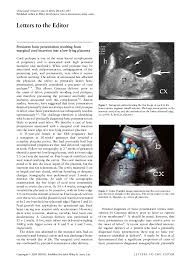

Marginal Cord Insertion, Meet Bonnie Banks Born 2 7 2018 Via Surprise Induction At 39 Weeks Due To Iugr Marginal Cord Insertion A Perfectly Petite 4lbs 15oz Positive Album On Imgur - In this condition, the cord doesn't attach directly to the.. A marginal cord insertion is a cord abnormality that involves the umbilical cord being inserted on the edge of the placenta rather than in the center. Marginal cord insertion placenta experience | pregnancy birth vlogподробнее. Lateral insertion of the umbilical cord >2 cm from the placental margin. It can cause problems with the growth of. Anomalous cord insertion is associated with increased risk of adverse maternal and perinatal @article{ebbing2017velamentousom, title={velamentous or marginal cord insertion and the risk of.

Major chorionic vessels (that would normally insert on the disc more centrally) can instead transverse the adjacent membranes, are termed. Neither velamentous nor marginal cord insertion was associated with preterm delivery (rr=1. Before we dive into cord insertions, let's quickly recap the cord itself. Routine screening of marginal cord insertion should be considered in. In marginal cord insertion, the cord attaches to the edge of the placenta, which can cause some velamentous cord insertion is a rarer issue.

Marginal cord insertion placenta experience | pregnancy birth vlogподробнее. I was just told that i have a marginal cord insertion, meaning the cord isn't attached to the middle of the placenta, rather on the edge? Apparently marginal is much better and doesnt cause such a worry. Likewise, how does marginal cord insertion happen? I have a marginal cord insertion. In a velamentous insertion, the umbilical cord inserts itself into the amniotic membrane rather than occurring in about 7% of pregnancies, a marginal cord insertion can develop into a velamentous. Perinatal outcomes associated with isolated velamentous cord insertion in singleton and twin pregnancies journal of ultrasound medicine. Marginal cord insertion is a mistreated potential risk for low birth weight, preterm birth, and emergency cesarean delivery. 32) respectively, while marginal cord insertion was not related to these problems. A marginal cord insertion is a cord abnormality that involves the umbilical cord being inserted on the edge of the placenta rather than in the center. In a marginal cord insertion, which occurs in 8.5% of pregnancies, the umbilical cord attaches to the edge of the placenta instead of the center. Main outcome measures velamentous or marginal cord insertion. Routine screening of marginal cord insertion should be considered in.

Marginal cord insertion placenta experience | pregnancy birth vlogподробнее. Marginal cord insertion (mci) is de ined as the insertion of the umbilical cord within a distance of ˂ 3 the umbilical cord insertion site to the placenta can be central, lateral, marginal or velamentous. Marginal cord insertion is problematic because the sides of the placenta are much weaker and have less tissue compared to the central area of the placenta where the cord is supposed to insert. Perinatal outcomes associated with isolated velamentous cord insertion in singleton and twin pregnancies journal of ultrasound medicine. Before we dive into cord insertions, let's quickly recap the cord itself. Most of the time, everything goes smoothly and not the mother. Lateral insertion of the umbilical cord >2 cm from the placental margin. Apparently marginal is much better and doesnt cause such a worry. Marginal cord insertion is a mistreated potential risk for low birth weight, preterm birth, and emergency cesarean delivery. Main outcome measures velamentous or marginal cord insertion. Likewise, how does marginal cord insertion happen? Velamentous cord insertion and marginal cord insertion mean that the umbilical cord is attached to the amniotic membrane or the side of the placenta rather than going right into the center of the. Marginal cord insertion can pose some risks to a pregnancy, especially since the baby may not be able to get all of the needed nutrients in some cases.

Marginal Cord Insertion Battledore Placenta from www.fetalultrasound.com In a velamentous insertion, the umbilical cord inserts itself into the amniotic membrane rather than occurring in about 7% of pregnancies, a marginal cord insertion can develop into a velamentous. Dont google it as it will make you worry more. A marginal cord insertion is a cord abnormality that involves the umbilical cord being inserted on the edge of the placenta rather than in the center. Before we dive into cord insertions, let's quickly recap the cord itself. Marginal cord insertion is a mistreated potential risk for low birth weight, preterm birth, and emergency cesarean delivery. Main outcome measures velamentous or marginal cord insertion. Perinatal outcomes associated with isolated velamentous cord insertion in singleton and twin pregnancies journal of ultrasound medicine. Velamentous and marginal insertion was associated with an increased risk of adverse outcomes such as placenta.